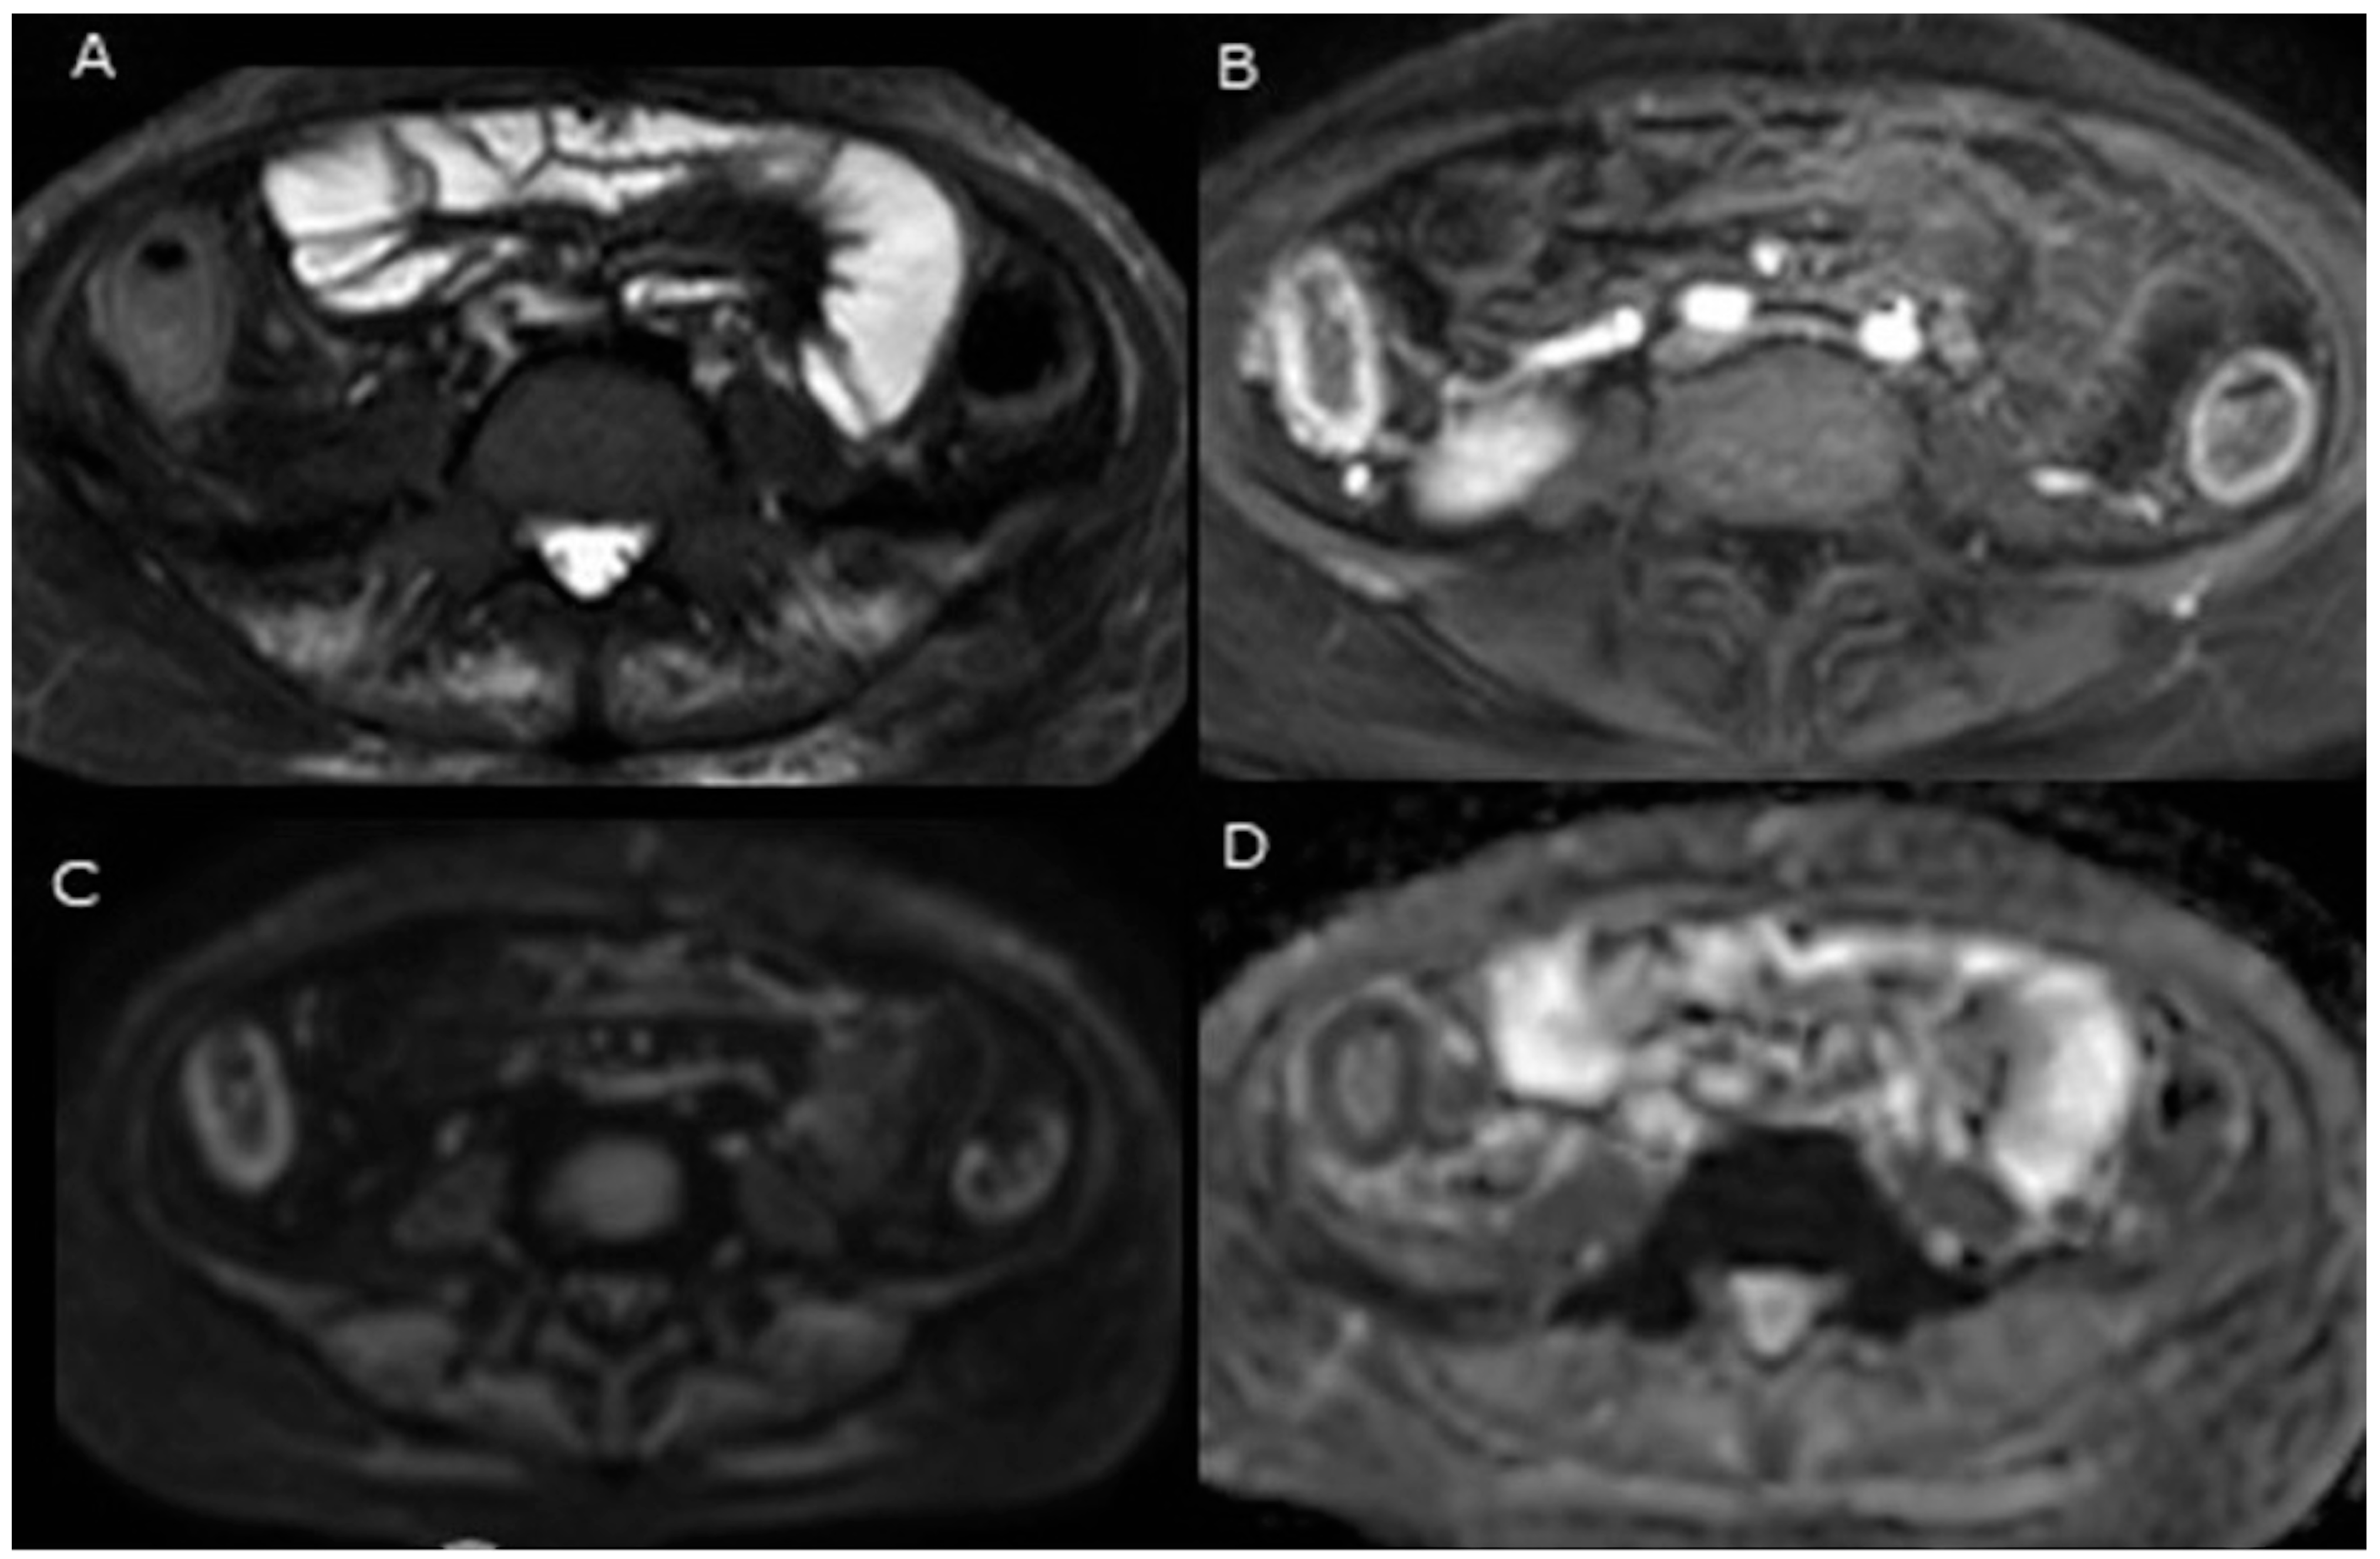

| Oussalah et al. [24] | 28 UC patients (105 segments) Prospective study | Colonoscopy 0 and 600 | No | The presence of hyperintensity on diffusion-weighted imaging (DWI) demonstrates a significant predictive value for endoscopic inflammation, as indicated by an odds ratio (OR) of 13.26 (95% CI: 3.6–48.93) and an area under the curve (AUC) of 0.854 (p = 0.0001). A total segmental magnetic resonance (MR) score of greater than 1 meant a sensitivity, specificity and AUROC of 89.47%, 86.67% and 0.920, respectively. The proposed total MR score correlated with the Walmsley index (r = 0.678, p < 0.0001) and the total modified Baron score (r = 0.813, p = 0.0001) in those patients. The presence of a DWI hyperintensity (DWI-HI) showed a sensitivity of 90.79% and a specificity of 80% for detecting endoscopic inflammation, with an AUROC of 0.854 (p = 0.0001) In detecting endoscopic inflammation, the DWI hyperintensity had the same accuracy as gadolinium-based contrast agent enhancement. The study concluded that the MR-DWI colonography rectal preparation or without oral could represent a non-invasive tool in evaluating colonic inflammation in UC. |

| Yu et al. [61] | 20 UC patients (100 segments) Prospective observational study | Colonoscopy 0, 400, 600, 800, and 1000 | No | DWI hyperintensity at a b-value of 800 s/mm2 reliably indicated the presence of endoscopic colonic inflammation, with a sensitivity of 93.0%, specificity of 79.3% and statistically significant AUC of 0.867 (p < 0.0001). The segmental MR score (MR-score-S) exhibited a significant positive correlation with the segmental modified Baron score (Baron-S) (r = 0.761, p < 0.0001). Similarly, the total magnetic resonance score (MR-score-T) demonstrated a strong positive correlation with the total modified Baron score (Baron-T) (r = 0.875, p < 0.0001). An MR-score-S greater than 1 was found to be indicative of endoscopic colonic inflammation, with a sensitivity and specificity of 85.9% and 82.8%, respectively, and an AUC of 0.929 (p < 0.0001). DWI hyperintensity at a b-value of 800 s/mm2 demonstrated significantly higher diagnostic accuracy compared to b-values of 400, 600 and 1000 s/mm2. The study determined that an ADC value of 2.18 × 10⁻³ mm2/s effectively identifies endoscopic inflammation, demonstrating sensitivity and specificity of 89.7% and 80.3%, respectively. For DWI hyperintensity, the inter-observer agreements across different b values were consistent, with kappa values ranging from 0.719 to 0.825. The ADC measurements obtained by the two radiologists were compared, revealing a Pearson’s correlation coefficient of 0.886 (p < 0.001), which indicates a high level of inter-observer agreement. They concluded that the integration of DWI with conventional MRI, without the need for bowel preparation, offers a quantitative approach to distinguishing actively inflamed intestinal segments from normal mucosa, enabling the detection of UC. |